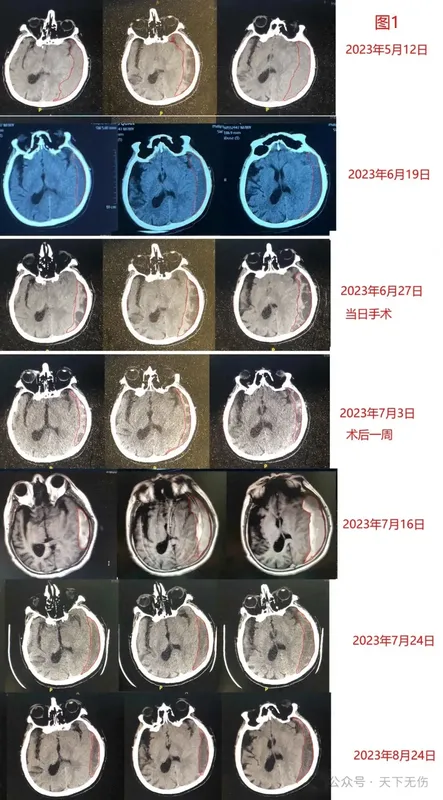

國(guó)各地求診于我的慢性硬膜下血腫患者數(shù)量在不斷增加,見(jiàn)過(guò)的患者多,各種情況就見(jiàn)得多,也因此遇到一些因應(yīng)用激素而導(dǎo)致患者疑慮、甚至自動(dòng)停藥,或者主管醫(yī)生拒絕用藥的情況;當(dāng)然更多的患者使用激素體驗(yàn)良好。L女士,69歲,是某著名醫(yī)院的著名專家,因摔傷頭部后被確診慢性硬膜下血腫。她不希望手術(shù)治療,來(lái)我門診治療。我看她的血腫量不太多,就開(kāi)具了他汀加激素治療方案。治療第1周的CT復(fù)查看到血腫沒(méi)有減少,反而略有增大。她坦白告訴我,她對(duì)激素有疑慮,沒(méi)有應(yīng)用。我為她做了解釋:我們用藥量很少,最多用4周,應(yīng)該不會(huì)對(duì)她造成永久性傷害。她聽(tīng)進(jìn)去我的解釋,開(kāi)始應(yīng)用激素,結(jié)果血腫越來(lái)越少(圖1)。2022年9月5日復(fù)查時(shí),血腫還沒(méi)有完全消失,但是她已經(jīng)正常上班。她抱怨吃激素后雙腳腫脹明顯,又覺(jué)得頭疼頭暈癥狀緩解,就自己停用了地塞米松。后來(lái)她沒(méi)有再回來(lái)復(fù)查過(guò),只是電話告知我,她已經(jīng)痊愈而且雙腳腫脹也已消除。H先生,43歲,因練習(xí)拳擊導(dǎo)致左顳部受傷后發(fā)展成慢性硬膜下血腫。他不想手術(shù),2024年10月24日輾轉(zhuǎn)從北京一家著名醫(yī)院來(lái)宣武找我門診。我給他開(kāi)具了他汀加激素藥物治療方案,叮囑他2周復(fù)查。他1周后就匆匆忙忙來(lái)復(fù)查。我看他的血腫較10月24日不僅沒(méi)有縮小,還疑似增加了,伴隨頭疼癥狀加重。問(wèn)診后才得知,他這一周主要是服用了阿托伐他汀鈣,沒(méi)有應(yīng)用激素。原因是他在口服地塞米松后不到一小時(shí),就渾身顫抖、心率加快,于是自停藥。我看他精神焦慮、頭疼明顯,就安排他住院接受手術(shù)治療。結(jié)果他非常害怕,并沒(méi)有去住院,反而是回到家中,重新?lián)炱鹞业乃〖拥厝姿煞桨福撕蟮拿看螐?fù)查,他的血腫都在減少,直到今年1月16日再次復(fù)查,確診他已經(jīng)治愈(圖2)。F先生,82歲,是某市知名糖尿病專家,他自己是糖尿病患者。他因外傷導(dǎo)致左側(cè)硬膜下血腫。老先生完全清醒,左下肢有些力弱(剛開(kāi)始我也納悶,左側(cè)血腫應(yīng)導(dǎo)致右下肢無(wú)力,為什么是左下肢無(wú)力?)。他的主管醫(yī)生征詢我意見(jiàn)后,我臨時(shí)加大了地塞米松的量。剛開(kāi)始,我還擔(dān)心老教授不愿意接受我主張的激素治療,畢竟它會(huì)干擾血糖血壓。但老教授告訴我,他搞了一輩子糖尿病,對(duì)激素的副作用完全知曉,而且自己可以調(diào)節(jié)血糖到基本正常,愿意接受我的他汀加激素治療方案。后續(xù)復(fù)查,眼見(jiàn)他的血腫逐步減少(圖3),左下肢力量也逐步增強(qiáng),我正期待他的最新復(fù)查結(jié)果。L女士,39歲,因頭部外傷導(dǎo)致左側(cè)慢性硬膜下血腫,于今年3月6日接受鉆孔引流術(shù),手術(shù)成功。她術(shù)前就有視力障礙,術(shù)后發(fā)現(xiàn)雙眼視力進(jìn)一步下降,已經(jīng)到了幾乎失眠的地步。她兩口子從外地跑到北京某著名眼科??漆t(yī)院診療,確診顱內(nèi)壓增高(400mmH2O),雙側(cè)視乳頭水腫,術(shù)后仍殘余硬膜下血腫。該眼科醫(yī)生推薦患者來(lái)找我,結(jié)果她在我診室內(nèi),就因顱內(nèi)壓增高而惡心嘔吐。我果斷收她入院,先排除顱內(nèi)靜脈竇血栓,給予激素消除視乳頭水腫,給予高滲鹽水降低顱內(nèi)壓,給予他汀消除殘余血腫。她的癥狀迅速減輕,并且告訴我,當(dāng)輸上激素時(shí),她自覺(jué)有一股清冽之氣從輸液的胳膊進(jìn)去,進(jìn)入顱內(nèi),眼睛就亮了。她是3月21日來(lái)北京那家醫(yī)院看病的,但找我看病用藥已經(jīng)是3月26日,3月29日復(fù)查CT已可見(jiàn)硬膜下血腫縮小,與癥狀消減完全符合,且僅僅治療3天(圖4)。再過(guò)2天,她的顱內(nèi)壓也降到了130mmH2O。我知道這種患者的視力恢復(fù),決定性的是正確而及時(shí)的康復(fù),她一定還會(huì)進(jìn)步。我果斷要求她出院去接受高壓氧治療聯(lián)合鼠神經(jīng)生長(zhǎng)因子注射。昨天患者出院了,她的頭痛、惡心嘔吐緩解了,視力也已部分恢復(fù)。Y老先生,96歲,是我國(guó)某醫(yī)學(xué)專業(yè)領(lǐng)域的泰斗級(jí)教授。他因?yàn)檩p微外傷發(fā)生左側(cè)硬膜下血腫,他的右手已經(jīng)不能持筷,也不能下地行走了。我建議他采用小劑量短療程激素配合阿托伐他汀鈣治療,但他有嚴(yán)重糖尿病,他的主治醫(yī)生不敢完全采納我的激素治療方案,也因此他的癥狀也就沒(méi)有緩解。我主動(dòng)聯(lián)系這位主治醫(yī)生,跟他解釋為什要用激素,他很快聽(tīng)取我的意見(jiàn),加上了小劑量激素。今天距離我會(huì)診這位前輩已是過(guò)去8天,也是他加上激素治療后的第3天。電話隨訪這位主治醫(yī)生獲悉,接受他汀加激素治療方案后,老主任的血糖一度突然升高到19mmol/L,讓所有關(guān)心主任的醫(yī)生都擔(dān)心了。這位主治醫(yī)師隨后將地塞米松改成更小劑量。今天證實(shí),老主任各方面機(jī)能、包括右手肌力已明顯緩解。我期待著一周后老主任的檢查結(jié)果給我一個(gè)驚喜。。地塞米松是1948年由美國(guó)科學(xué)家菲利普·肖瓦爾特·亨奇(PhilipShowalterHench)和愛(ài)德華·卡爾文·肯德?tīng)枺‥dwardCalvinKendall)成功從腎上腺皮質(zhì)中分離得到,并發(fā)現(xiàn)其具有顯著的抗炎作用,1950年獲得諾貝爾生理學(xué)或醫(yī)學(xué)獎(jiǎng)。1960年代,地塞米松被批準(zhǔn)用于治療多種炎癥和免疫相關(guān)疾病,地塞米松能有效減輕腦腫瘤或腦外傷引起的腦水腫,因此神經(jīng)外科常應(yīng)用它來(lái)自治療腦水腫;在腫瘤領(lǐng)域,則被用于治療化療或放療后并發(fā)癥。我國(guó)非典流行期間和COVID-19疫情中,曾廣泛應(yīng)用地塞米松治療感染患者;而英國(guó)學(xué)者報(bào)道,地塞米松可使重癥COVID-19患者的死亡率降低約1/3。地塞米松最為令人擔(dān)憂的副作用是股骨頭壞死。有統(tǒng)計(jì)認(rèn)為,長(zhǎng)期使用較大劑量的糖皮質(zhì)激素患者中,股骨頭壞死的發(fā)生率約為3%~34%。如果應(yīng)用地塞米松的劑量超過(guò)每天3mg,長(zhǎng)期使用的話,股骨頭壞死的發(fā)生率可達(dá)5%-25%。地塞米松治療慢性硬膜下血腫始于1960年代加拿大醫(yī)生的發(fā)明,而且迄今在北歐、北美還被廣泛用來(lái)預(yù)防或者治療慢性硬膜下血腫術(shù)后復(fù)發(fā)。2020年劍橋大學(xué)團(tuán)隊(duì)發(fā)表臨床研究結(jié)果認(rèn)為地塞米松相比于安慰劑沒(méi)有促進(jìn)慢性硬膜下血腫吸收,且地塞米松應(yīng)用后死亡率較對(duì)照組高,但是,劍橋團(tuán)隊(duì)在19天內(nèi)應(yīng)用地塞米松的總劑量達(dá)到了110.5mg。我認(rèn)為,激素治療慢性硬膜下血腫歷史久遠(yuǎn),且今天歐美醫(yī)生還在應(yīng)用,該方案具有生命力。雖然其副作用讓人生畏,但降低劑量則可能避免或減輕,因此,我提出了以阿托伐他汀鈣為主、以小劑量地塞米松為輔的阿托伐他汀鈣聯(lián)合地塞米松治療慢性硬膜下血腫新方案,4周的地塞米松總劑量最多是49mg,不及劍橋團(tuán)隊(duì)報(bào)道的地塞米松劑量的一半。我從2009年開(kāi)始他汀為基礎(chǔ)的藥物治療慢性硬膜下血腫研究,治療的患者數(shù)量已經(jīng)超過(guò)1400余例,而從2014年開(kāi)始的地塞米松與阿托伐他汀鈣聯(lián)合方案治療慢性硬膜下血腫患者,其數(shù)量已近千例,但僅有1例患者發(fā)生疑似發(fā)生地塞米松相關(guān)股骨頭壞死。這位患者僅接受過(guò)4周的他汀加地塞米松藥物治療,治療期間無(wú)并發(fā)癥。3年后隨訪發(fā)現(xiàn)他罹患右側(cè)股骨頭壞死,是否跟激素有關(guān)?我至今不敢確認(rèn)。我特別理解醫(yī)生和患者對(duì)地塞米松應(yīng)用的顧慮,地塞米松除了可能誘導(dǎo)股骨頭壞死,還可能擾亂血糖代謝、心率和血壓,但是,地塞米松藥物相關(guān)副作用均與劑量和療程密切相關(guān),我們的實(shí)踐證明,我們的短期、小劑量應(yīng)用方案對(duì)于絕大多數(shù)慢性硬膜下血腫患者是可靠、有效和安全的,而且多數(shù)患者加上激素療效良好。我會(huì)繼續(xù)應(yīng)用該方案治療慢性硬膜下血腫患者,但也會(huì)更加關(guān)注其安全性專家介紹江榮才教授?首都醫(yī)科大學(xué)宣武醫(yī)院神經(jīng)外科二級(jí)教授,主任醫(yī)師,博導(dǎo)?首都醫(yī)科大學(xué)宣武醫(yī)院神經(jīng)外科神經(jīng)外科副主任兼任危重癥中心主任?中華醫(yī)學(xué)會(huì)神經(jīng)外科學(xué)分會(huì)委員、腦外傷學(xué)組副組長(zhǎng)?中國(guó)醫(yī)師協(xié)會(huì)神經(jīng)外科醫(yī)師協(xié)會(huì)神經(jīng)重癥專委會(huì)副主任委員?國(guó)家創(chuàng)傷醫(yī)學(xué)中心顱腦創(chuàng)傷專業(yè)委員會(huì)副主任委員?中國(guó)老年保健協(xié)會(huì)神經(jīng)外科學(xué)創(chuàng)新與轉(zhuǎn)化分會(huì)首任會(huì)長(zhǎng)?擅長(zhǎng)復(fù)雜重型腦外傷、腦出血及慢性硬膜下血腫的診療。?是他汀治療硬膜下血腫的主要發(fā)明者,治療慢性硬膜下血腫患者超1400名,總治愈率約90%?!境鲈\時(shí)間】每周四下午(神經(jīng)外科專家門診)每周三上午(神經(jīng)外科特需門診)